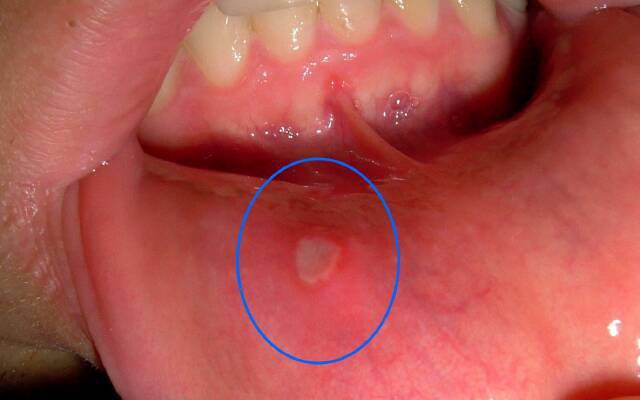

Nos adultos, manifesta-se como a formação de pequenas feridas redondas - as aftas, que têm uma tonalidade branca ou amarelada com uma borda vermelha. Às vezes ocorre com danos mecânicos à frente da cavidade oral: nos lábios, bochechas e na ponta da língua. A maioria dos médicos está inclinada a acreditar que a etimologia da estomatite aftosa é viral, chamando as causas de adenovírus, uma infecção por herpes.

O curso crônico da doença em adultos com recidivas frequentes indica a presença de doenças gastrointestinais ou hepáticas. Manifesta-se por tais sintomas: lesões múltiplas dos lábios, bochechas, língua; dor que interfere na ingestão de alimentos; aumentando a temperatura do corpo para 38. O tratamento da estomatite em casa inclui um conjunto de medidas relacionadas a sinais sintomáticos, fortalecendo a imunidade.